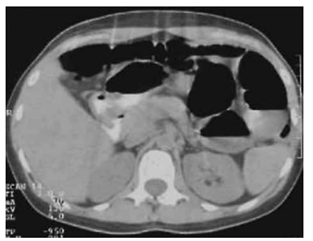

Paciente de 64 anos, portadora de diabetes mellitus tipo 2, hipertensão arterial, hiperuricemia e hipertrigliceridemia, é submetida a colectomia segmentar por neoplasia de cólon há 5 dias. Evolui com febre persistente, dor abdominal progressiva e inapetência na enfermaria. Nas últimas 12 horas, apresentou vômitos biliosos e rebaixamento do nível de consciência sendo transferida para unidade de terapia intensiva.

Ao exame físico: PA: 78 x 50 mmHg; FC: 124 bpm; FR: 28 irpm; SatO₂: 94% O₂ nasal; temperatura: 38,9 °C; pele fria; tempo de enchimento capilar 5 s; Glasgow: 13; abdome: distendido, doloroso difusamente, sinais de defesa involuntária e descompressão brusca dolorosa. Exames laboratoriais iniciais: lactato: 5,2 mmol/L; leucócitos: 24.000/mm³; plaquetas: 88.000/mm³; creatinina: 2,3 mg/dL (VR <1,2); bilirrubina total: 2,1 mg/dL.

Realizou a tomografia de abdome sem contraste a seguir:

Enunciado 4925927-1

(Arquivo pessoal; imagem usada com autorização)

Qual é a medida fundamental, associada à antibioticoterapia e ao suporte hemodinâmico, para o manejo desse caso?